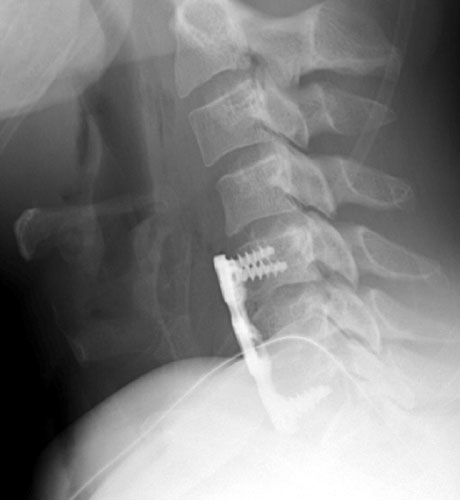

40 y.o. male with history of falling off a truck while doing some work had

complained of low back pain, muscle spasm, hand and feet numbness, and neck pain

since the time of the action. Patient underwent C5-6 and C6-7 anterior cervical

discectomy with fusion using anterior plating.

Lateral film showing the intact plate and screws for the fusion and

nearly imperceptible grafting material in the disc spaces of C5-6 and C6-7. |